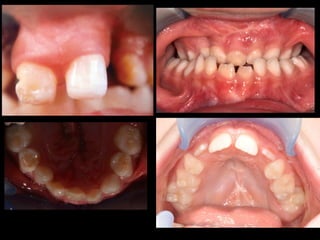

When looking to the condyle from an anterior view, one can see the oblong

shape of a condyle but the left condyle is smaller.

!

The midline are not coincident. Note that the lower midline is toward right like

the occlusal plane canting to the right. This can be explained by the lack of

heigh of the left ramus and as normal growth occur, there is a wagon wheel

effect and the midline deviate toward the normal side, the occlusal plane is

moving up on the affected side.